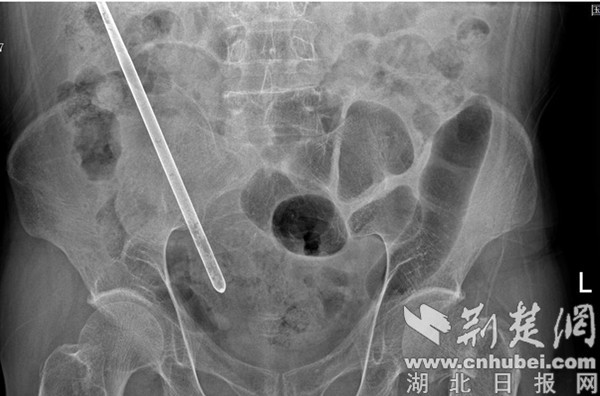

荊楚網(wǎng)(湖北日?qǐng)?bào)網(wǎng))訊(通訊員 胡祖超) 一根長23厘米的鐵筷子,在王老漢的腹中“躺”了七年之久,時(shí)隔七年終于被國藥漢江醫(yī)院外二科成功取出。近日,王老漢不小心跌倒,左髖部疼痛難忍,遂就診國藥漢江醫(yī)院外一科。X線提示讓人匪夷所思,不僅左股骨頸頭下骨折,還發(fā)現(xiàn)腹腔有一筷子形狀的金屬物。

X線提示腹腔有一筷子形狀的金屬物。 通訊員 供圖